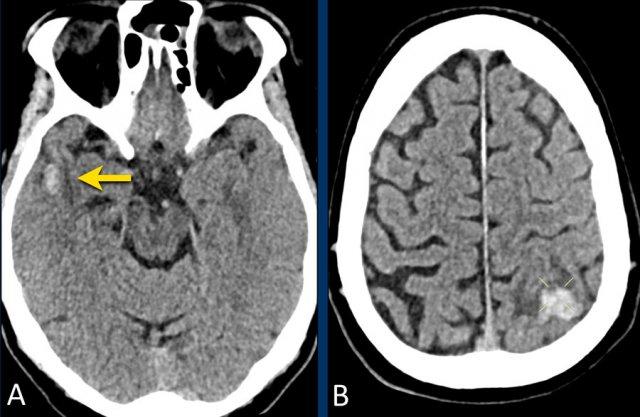

Bệnh nhân CAA này nhập viện với hình ảnh khối máu tụ thùy lớn ở thùy thái dương phải.

Lưu ý hình ảnh nhiễm sắt bề mặt (mũi tên).

Bệnh nhân CAA này có xuất huyết vi thể, nhiễm sắt bề mặt và nhiều ổ nhồi máu.

Lưu ý ổ xuất huyết ở cầu não (mũi tên vàng).

Có hình ảnh nhiễm sắt bề mặt ở vùng chẩm trái.